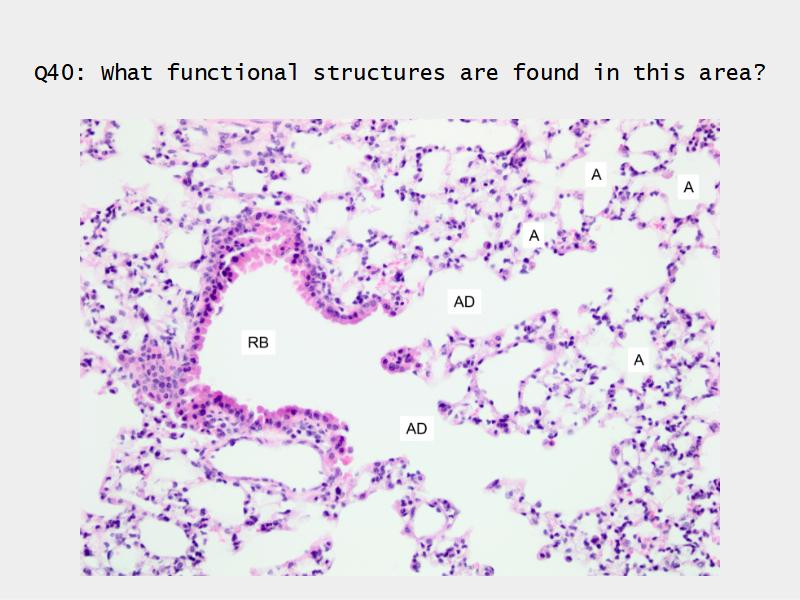

Components of the Blood-Air Barrier?

- Respiratory bronchioles

- Conducting -> Respiratory

- Simple cuboidal epithelium

- Secretory cells

- Alveoli

Lungs